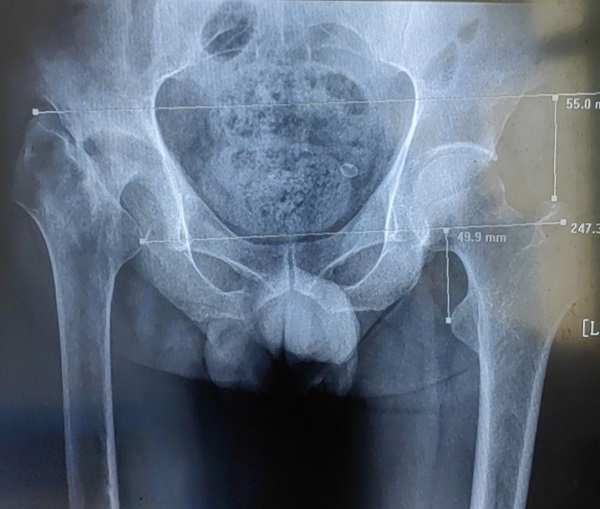

李师傅病程长,情况复杂,检查发现其骨盆倾斜,股骨头、颈部分缺如,髋臼严重骨缺损,髋关节半脱位,患肢短缩近6cm,髋关节周围软组织挛缩。手术难度大,髋部股神经、坐骨神经以及股动脉牵张损伤的风险很大,创伤骨科郭永良主任和王争刚主任医师经过充分术前讨论,制定出了细密的个性化手术方案,并与患者及家属充分交流和沟通。